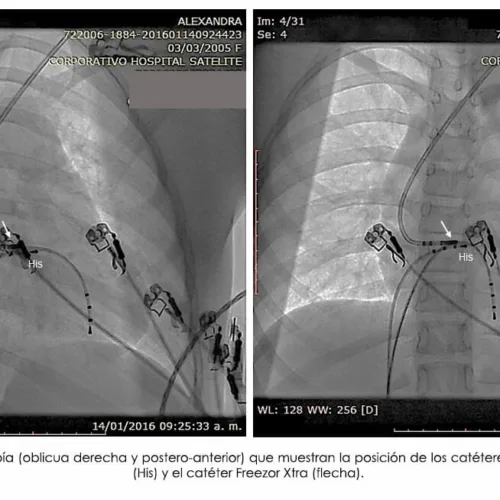

Avanzando en Precisión y Cuidado: La Revolución de la Imagen Médica en Hospital Satélite